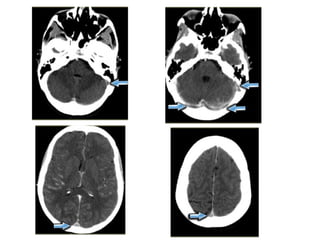

The same patient , there is absence of flow void in the internal

cerebral veins, straight sinus and right transverse sinus (blue

arrows) , on the MRA the right transverse sinus is not visualized